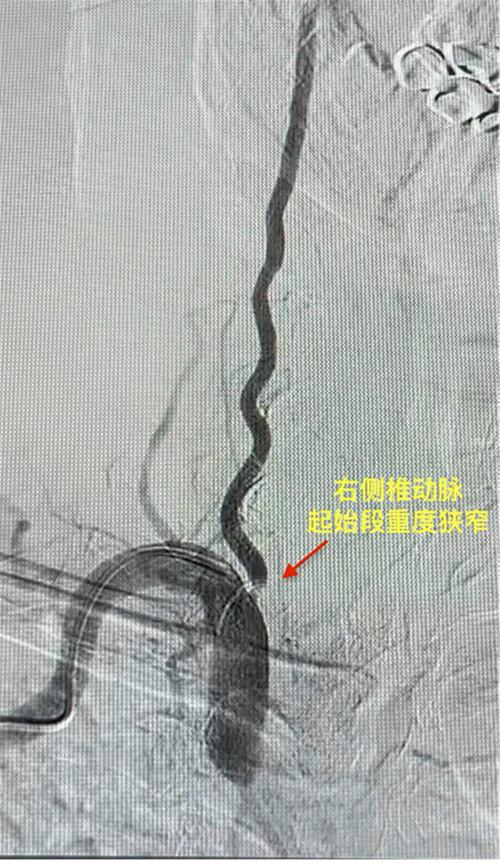

内江市市中区人民医院完成首例椎动脉狭窄支架植入术

微甜城

|

2024/02/22 17:46

1552点击